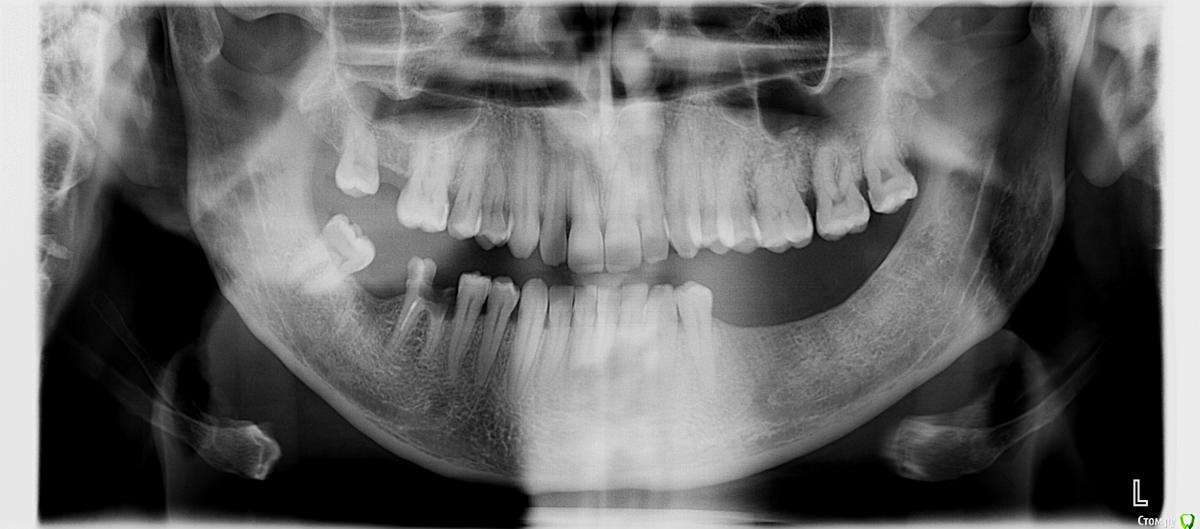

Алексей81 Опубликовано 28 июля, 2015 Автор Поделиться Опубликовано 28 июля, 2015 А что можно сказать по этому снимку? Ссылка на комментарий

shishok Опубликовано 28 июля, 2015 Поделиться Опубликовано 28 июля, 2015 Очень большая вероятность наличия кариозной полости на передней поверхности левой восьмерки. Ссылка на комментарий

Алексей81 Опубликовано 29 июля, 2015 Автор Поделиться Опубликовано 29 июля, 2015 Хирург с которым я говорил, сказал что у меня там (3 верхних коренных зуба с лева) киста и воспаление, хронический периодонтит, (если с названием не ошибся) на следующей недели поеду к нему на операцию, будем все удалять. Ссылка на комментарий

red_butler Опубликовано 29 июля, 2015 Поделиться Опубликовано 29 июля, 2015 показаний для удаления не увидел Ссылка на комментарий